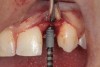

When the patient was 18 years old, an implant was placed in site No. 10 with no complications (Figure 9 and Figure 10). Three months later, a periapical radiograph was taken, the implant was torque tested, and a healing abutment (3 mm by 4 mm by 4 mm) was placed.

Fig 9 and Fig 10. An implant placed in site No. 10.